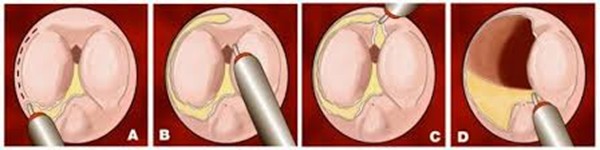

Această intervenție este realizată sub anestezie generală sau rahidiană. Medicul urolog introduce la nivelul canalului uretral un aparat numit endoscop care îi permite vizualizarea uretrei si reperarea prostatei. Cu ajutorul unei fibre laser medicul urolog poate introduce endoscopul între adenomul de prostată și capsula prostatei. Astfel, făcând tot turul adenomului de prostată, medicul urolog detașează adenomul de capsula prostatei și împinge adenomul în vezica urinară. Adenomul complet liber este extras cu ajutorul unui instrument ce se numește morcelator, care permite morcelarea (tăierea) adenomului de prostată în mici fragmente ce pot fi extrase prin aspirare prin interiorul endoscopului.

Fragmentele de prostată extrase sunt trimise pentru a fi analizate histopatologic. O sondă uretro-vezicală cu trei căi este montată la finalul intervenției.